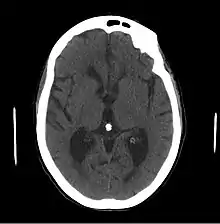

- Le scanner cérébral peut montrer une dilatation ventriculaire disproportionnée par rapport à l’atrophie corticale avec élargissement des cornes frontales et arrondissement des cornes temporales sans atrophie de l'hippocampe.